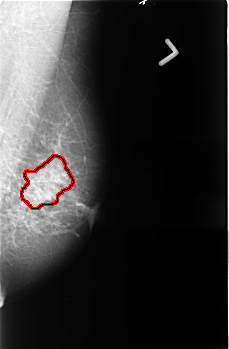

B_3397_1.LEFT_CC

LEFT_CC LINES 4584 PIXELS_PER_LINE 2984 BITS_PER_PIXEL 12 RESOLUTION 50 OVERLAY

FILE: B_3397_1.LEFT_CC.OVERLAY

TOTAL_ABNORMALITIES 1

ABNORMALITY 1

LESION_TYPE CALCIFICATION TYPE PLEOMORPHIC DISTRIBUTION SEGMENTAL

LESION_TYPE MASS SHAPE FOCAL_ASYMMETRIC_DENSITY MARGINS ILL_DEFINED

ASSESSMENT 5

SUBTLETY 4

PATHOLOGY MALIGNANT

TOTAL_OUTLINES 1

BOUNDARY